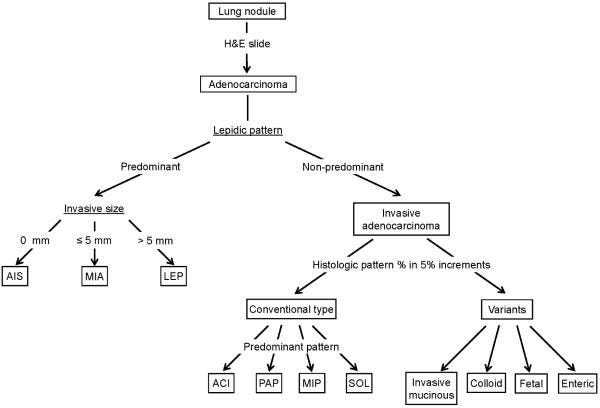

🫣 Počul si o AIS a MIA?

Nie, nemyslím akademický informačný systém, ani moderné dievčenské meno! 😜

AIS – adenokarcinóm in situ v pľúcach. Je to malý (≤ 30 mm), lokalizovaný adenokarcinóm s nádorovými bunkami rastúcimi výlučne po povrchu existujúcich pľúcnych alveolov (tzv. lepidický rast). Stromálna, cievna alebo pleurálna invázia nie je prítomná!

MIA – minimálne invazívny adenokarcinóm pľúc. Podobne: je to malý, solitárny adenokarcinóm (≤ 30 mm) s prevažne lepidickým rastom a veľkostne limitovanou stromálnou inváziou (≤ 5 mm).

🧐 Na správnu diagnózu AIS a MIA je potrebný resekát časti pľúc, aby sa histopatologicky vyšetrila kompletne celá lézia! Tieto diagnózy sa nemôžu stanoviť z malých bioptických vzoriek alebo cytologických preparátov.

Ak chceš vedieť, čo je to lepidický rast, klikni link na video v nasledujúcej časti. 👇